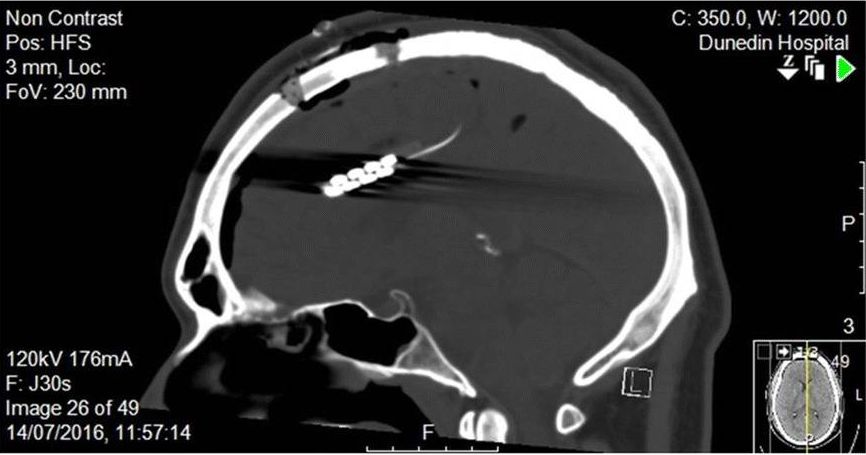

Lesions in the anterior cingulate cortex (ACC) have been linked to impaired decision making and the arisal of impulse control issues, as the ACC appears to be instrumental in error detection. Issues in the ACC are thus more likely to result in faulty or flawed decisions and judgements passing by uncorrected. Incidentally, the ACC was found to be heavily affected by environmental tetraethyl lead contamination, underlying the theory that leaded gasoline was responsible for a surge in crime until this additive was discontinued.

Abnormal activity in the ACC has for example been associated with alcohol addiction, with an implant suggested to adjust said neural activity as detailed in a 2020 Neurotherapeutics study by Sook Ling Leong et al. In this study the eight treatment-resistant alcoholics had electrodes inserted into part of their ACC to provide direct stimulation, leading to a self-reported 60% drop in cravings.

From this we can thus deduce that activity in the ACC is not only essential for decision-making, but it also illustrates how the pinkish goop in our skulls is a fascinating biochemistry and neurochemistry experiment in which the addition or subtraction of certain substances and poking it with electrodes can induce a wide variety of cognitive outcomes.